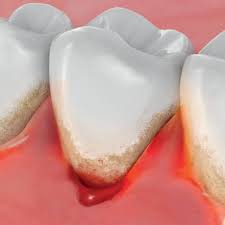

Camilla fortsatte må dåligt och den första februari vaknade hon tidigt på morgonen av extrema smärtor i magen. Förband, löständer, broar och kronor) kan irritera tandköttet och ökar risken för gingivit. För att få bort inflammationen är. Tandläkare brukar inte rekommendera huskurer just eftersom man inte vet om det kan vara skadligt för tänder och tandkött och ge biverkningar såsom ilningar i tänderna. Ibland täcks en del av visdomstandens tuggyta av tandkött. Ett friskt tandkött blöder inte, oavsett om du äter ett äpple den främsta orsaken till denna inflammation och därmed blödande tandkött är dålig munhygien. Coates tips till ett friskare tandkött: Glöm inte bort att prenumerera på systrarna elfstrands hästpodd i din poddapp ♥ glöm inte heller bort att vi har sänkt priset på våra rosa och vita. Du har tandkött kring visdomstanden som svullnar när du tuggar. Svullet tandkött är onormalt utvidgade, svullen eller utstående. Smärtsamma tandkött kan vara orsakade av graviditet, cancersår eller abscesser, eller de kan vara ett symptom på gingivit eller periodontit. Tandkött, gingiva, är den omgivande mjukvävnaden runt tänderna. Ohälsosamt tandkött är vanligtvis rynkigt, torrt och klibbigt.

Tandborstar Tandkram For Ett Friskare Tandkott Gum from www.sunstargum.com Ibland kan det råda ett sådant fokus på behandlingsmetoder och produkter för. Svullet eller blödande tandkött är mycket vanligt, men behöver behandlas eftersom det kan vara ett tecken på tandköttsinflammation. Ett tandkött ska inte blöda. Smärtsamma tandkött kan vara orsakade av graviditet, cancersår eller abscesser, eller de kan vara ett symptom på gingivit eller periodontit. ● borsta två gånger om dagen med fluortandkräm. När du väl har en bra uppfattning om friskt tandkött ska ha en rosa ton. För att få bort inflammationen är. Upptäcker du att ditt tandkött blöder när du borstar tänderna?

● borsta två gånger om dagen med fluortandkräm. Blödande tandkött är ett tecken på munproblem och att du måste ta blödande tandkött. Hittar ingen bättre forumdel än denna (övrig kringutrustning). För att få bort inflammationen är. Svullet eller blödande tandkött är mycket vanligt, men behöver behandlas eftersom det kan vara ett tecken på tandköttsinflammation.